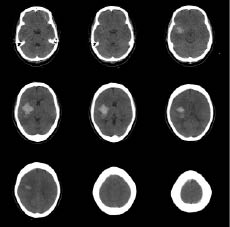

A 52-year-old woman with right-hand dominance and no significant medical history was brought to the emergency room following the sudden onset of left-sided weakness and loss of consciousness. The patient initially scored 11 points in the Glasgow Coma Scale (GCS): 4 for eye blinking, 5 in response to verbal command, and 2 for motor function; the Manual Muscle Test (MMT) revealed trace muscle movement in the upper and lower extremities. Computed tomography (CT) of the brain revealed a haematoma of approximately 40 ml in the right basal ganglia area and collapsed brain around the right lateral ventricle (Fig. 1). Burr-hole aspiration was performed to treat the haematoma. The patient was started on nimodipine (a calcium channel blocker) and depakote chrono (valproic acid, an anti-epileptic drug) to prevent seizures. The patient’s GCS score improved to 15, but MMT showed a poor grade for all extremities. Repeated serial CT scans showed complete resolution of the haematoma and no recurrence of bleeding. The patient was released from hospital without multidisciplinary rehabilitation treatment due to financial difficulties, with the intention of obtaining treatment at a public social facility.

Fig. 1. Initial computed tomography scan of brain disclosed about 40 ml haematoma at right basal ganglia and brain collapse around right lateral ventricle.